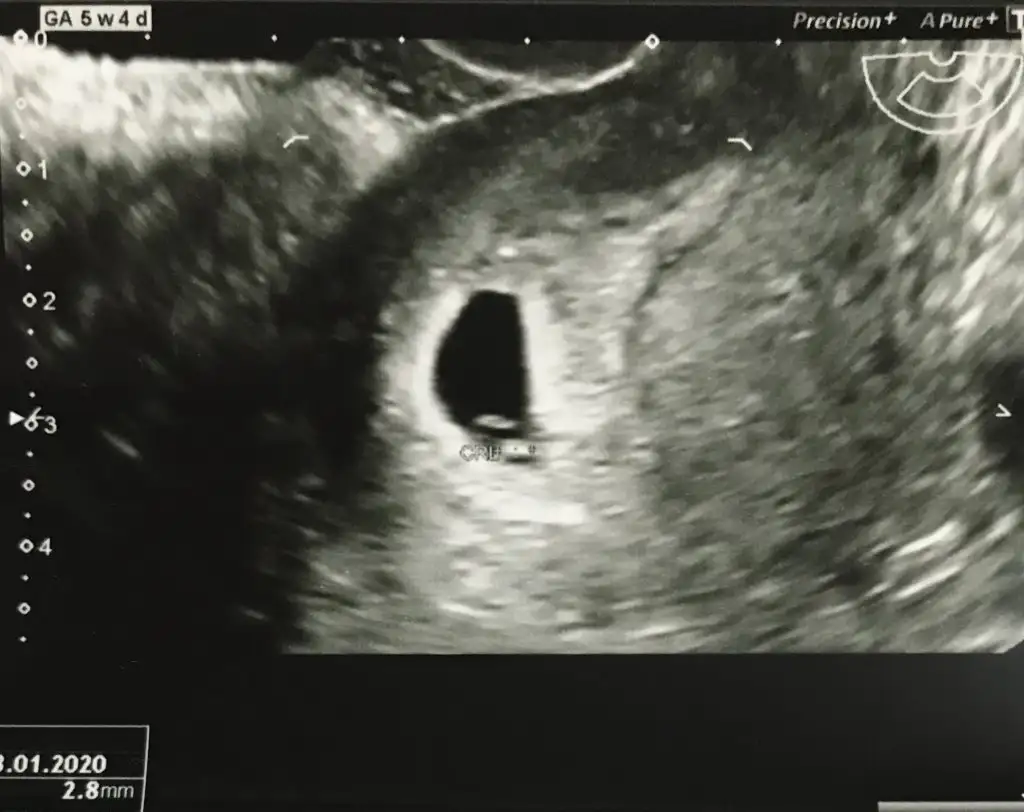

eklediğim fotolar vajinal ultrasondan ve burada 5+4 haftalık:)

Şimdiden teşekkür ediyorum...

Ayy çok teşekkür ederim en azından fikir verdiniz bana sağlıkla gelsin inşallah :) peki neye göre sağda ve ya solda diyoruz onu da sorsam size sanırım anlıyorsunuz bu konudan :)Sagada ama vajinal oldugu için asıl solmuş buna göre erkek

Nubu karanlık kalmış başka usg varmı

Ben kese konumunu pek tuttugunu sanmıyorum ben nub tahmini yapıyorum 11 yada 12 hafta olmalı kesede yolk saç nerde ise yani sag tarafta hafif kabarık beyaz parlak alan sagda tabi siz vajinal bakıldıgı için asıl solda olmuş oluyor karından bakılınca asıl sol olmuş olacaktı ve erkekAyy çok teşekkür ederim en azından fikir verdiniz bana sağlıkla gelsin inşallah :) peki neye göre sağda ve ya solda diyoruz onu da sorsam size sanırım anlıyorsunuz bu konudan :)